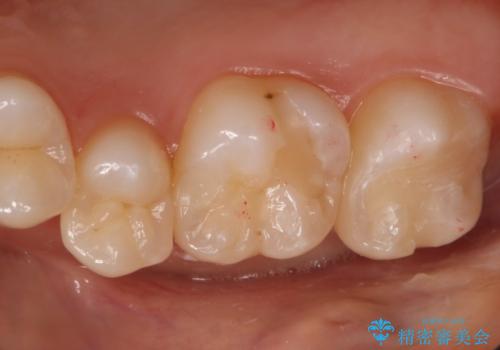

奥歯の保険の詰め物を自費のものに変えたい

- 右上6番の保険材料で詰められた部分をセラミックにやり変え希望の患者様です。

切削量などを考慮し、セラミックインレーでの治療を選択しました。

う蝕が深くまで進行していたので、全て除去した上でCR裏層を行い形成、印象を行っています。